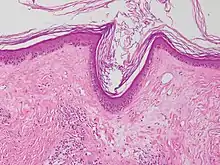

| Lichen sclerosus | Hyperkeratosis, atrophic epidermis, sclerosis of dermis and dermal lymphocytes.[3] |  | ||